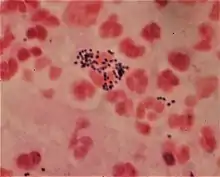

Gram staining differentiates bacteria by the chemical and physical properties of their cell walls. Gram-positive cells have a thick layer of peptidoglycan in the cell wall that retains the primary stain, crystal violet. Gram-negative cells have a thinner peptidoglycan layer that allows the crystal violet to wash out on addition of ethanol. They are stained pink or red by the counterstain,[2] commonly safranin or fuchsine. Lugol's iodine solution is always added after addition of crystal violet to strengthen the bonds of the stain with the cell membrane.

Gram-positive bacteria have a thick mesh-like cell wall made of peptidoglycan (50–90% of cell envelope), and as a result are stained purple by crystal violet, whereas gram-negative bacteria have a thinner layer (10% of cell envelope), so do not retain the purple stain and are counter-stained pink by safranin. There are four basic steps of the Gram stain:

After decolorization, the gram-positive cell remains purple and the gram-negative cell loses its purple color.[16] Counterstain, which is usually positively charged safranin or basic fuchsine, is applied last to give decolorized gram-negative bacteria a pink or red color.[2][17] Both gram-positive bacteria and gram-negative bacteria pick up the counterstain. The counterstain, however, is unseen on gram-positive bacteria because of the darker crystal violet stain.